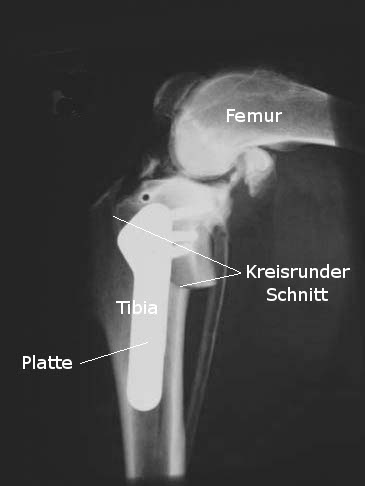

Bei der Tibial Plateau Leveling Osteotomy (TPLO) wird die Neigung der oberen Gelenkfläche des Schienbeins, des sogenannten Tibiaplateau, verändert: Dieses ist natürlicherweise nach hinten abgeschrägt, so dass der auf dieser Fläche aufsitzende Oberschenkel durch die auftretenden Scherkräfte nach hinten „rutschte“, wenn er nicht vom vorderen Kreuzband davon abgehalten würde. Die Verringerung dieser Neigung durch das Abflachen der Neigung des Tibiaplateaus hat zur Folge, dass die Stabilisierungsfunktion des vorderen Kreuzbandes durch das hintere Kreuzband und die Muskeln übernommen werden kann, weil die Scherkräfte verringert werden. Die Technik besteht im Prinzip darin, dass ein kreisförmiger Schnitt durch die Tibia erfolgt und der oberen Knochenanteil ein wenig gedreht und dann mit einer Metallplatte wieder am unteren Anteil fixiert wird. Die TPLO wird oft bei großen aktiven Hunden bevorzugt angewendet. | |

| Röntgenbild einer Tibial Plateau Leveling Osteotomy (TPLO) (Quelle: Dr Hellmuth Steger) |